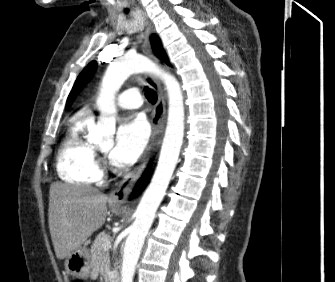

Мультиспиральная компьютерная томография – это современный высокоинформативный рентгенологический метод диагностики различной патологии легких. КТ основана на применении рентгеновского излучения. Однако в отличие от обычного рентгена, при котором снимки делаются в одной плоскости и изображения органов могут накладываться друг на друга, КТ лишена этих недостатков, так как во время компьютерной томографии сканирование проводится в различных плоскостях.

Во время исследования рентгеновская трубка томографа вращается вокруг исследуемой области и производит множество послойных снимков с шагом 0,5-1 мм. Полученные снимки поперечного сечения с помощью компьютерной программы могут быть преобразованы в 3D-изображения исследуемого органа или участка ткани. Это позволяет выявлять практически все заболевания легких на ранних стадиях и назначать своевременное лечение.

В некоторых случаях, например, при подозрении на опухолевый процесс, проводится КТ легких с контрастированием, когда для лучшей визуализации патологического очага пациенту внутривенно вводится йодсодержащий контрастный препарат. Контрастное вещество накапливается в патологических участках и обеспечивает их яркую визуализацию на фоне неизмененной ткани. С помощью контрастирования можно визуализировать кровеносные сосуды, выявить первичные опухоли и метастазы в легких, дифференцировать новообразования, например, отличить доброкачественную опухоль от злокачественной.

В медицинском центре «Доступная медицина» установлено современное оборудование – 64-срезовый и 128-срезовый компьютерные томографы TOSHIBA AQUILION, на которых проводится сканирование легочной ткани. За счет увеличенного количества детекторов аппараты производят снимки с большой скоростью и минимальной дозой облучения. При этом инновационные цифровые приложения позволяют получить объемные изображения легочной ткани высокой четкости, контрастности и в мельчайших подробностях.